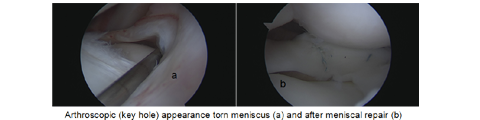

Knee arthroscopy is one of the most commonly performed surgical procedures. In it, a miniature camera (arthroscope) is inserted through a small puncture hole (portal). The camera allows for detailed examination of the knee. Your orthopaedic surgeon inserts miniature surgical instruments through other portals to confirm the type and location of the tear. Once he has done so he will either trim or repair the tear.

Meniscus repair: Some meniscus tears can be repaired by suturing (stitching) the torn pieces together. Whether a tear can be successfully treated with repair depends upon the type of tear, as well as the overall condition of the injured meniscus.